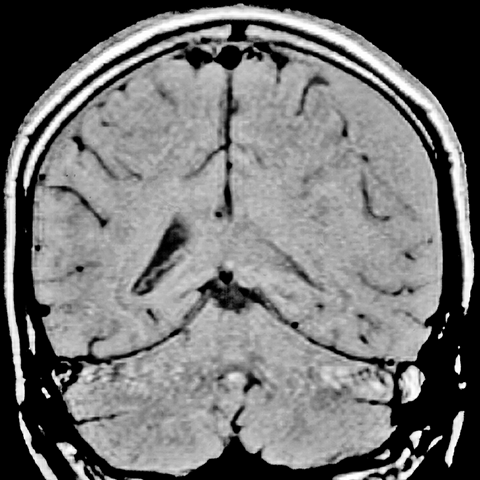

Subdural Hematoma [3 of 3]